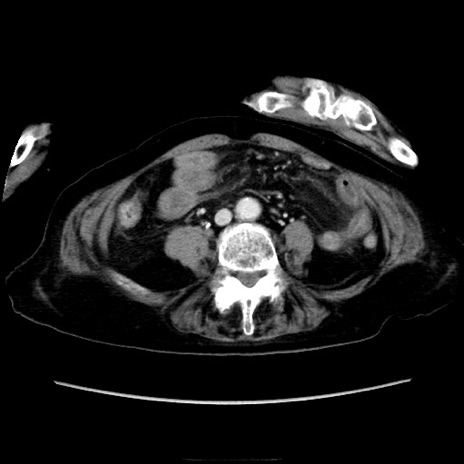

症例40(横断像)

【症例】90歳代女性

【主訴】腹痛・嘔吐

【現病歴】 食欲低下、嘔吐があり昨日他院受診。肺炎と診断され入院となる。入院後より腹部全体に圧痛あり。胃管留置され経過みていたが、症状持続するため、

当院転院となる。

【既往歴】胸椎圧迫骨折、胆石症

【身体所見】腹部:中央に激痛あり、圧痛あり、反跳痛不明

【データ】WBC 17100、CRP 18.82

横断像